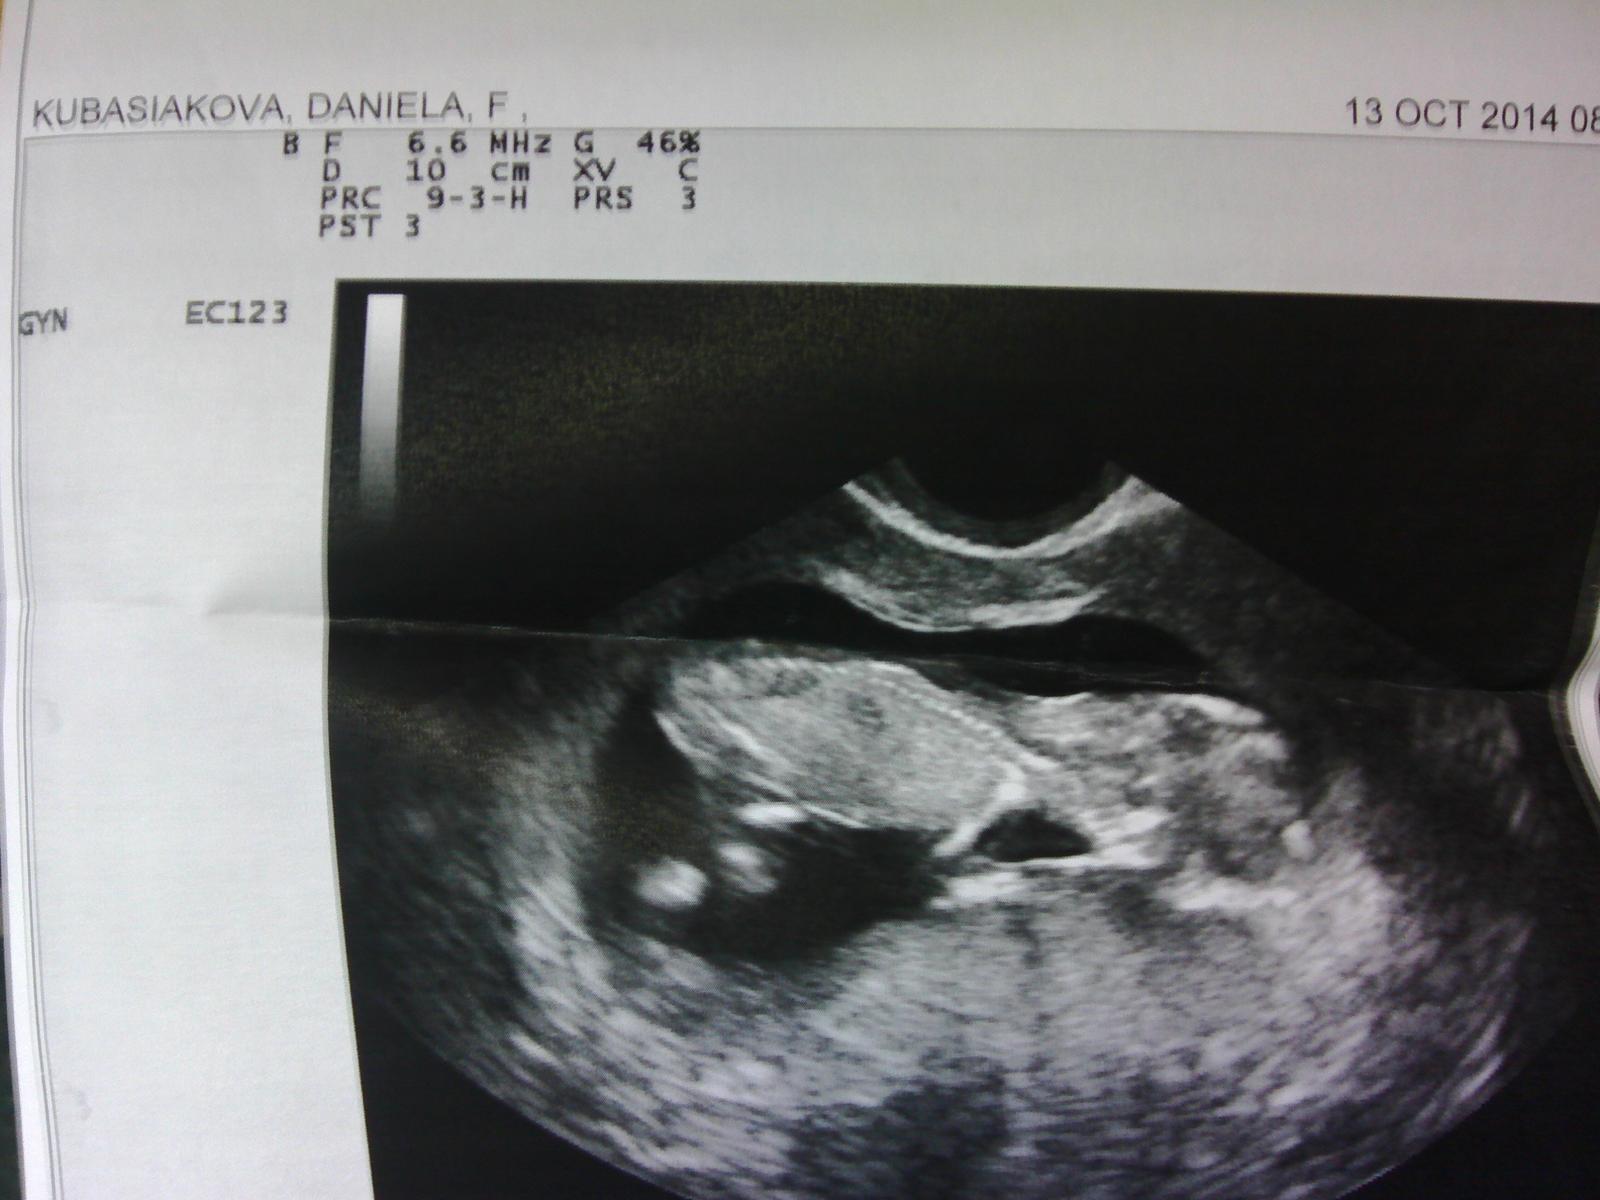

@acerka11 Babulky, pridávam foto nášho drobčeka a jeho prechodného bydliska 😀 dnes máme oficiálne prvý trimester ukončený, babo je akčné, rastieme...Veľmi sa teším,no viem, že vám to možno nieje príjemné čítať...Želám vám čím skôr podobné pocity, veron, seraa nesmuťte, príde to vtedy keď to budete najmenej čakať, tiež som si prešla kadečim, aj s mužom sme mali krizu ,no nevzdávajte sa, ok? Prvoradá je hlava a potom to ostatné. .Viem to podľa seba...Držim vám palce, aby ste sa dali aj po zdravotnej stránke obe dokopy, a potom už len huraaa milkovat sa 😉 Budem vás bombardovať správami ako sa máte a ako pokračujete 😉 Držkajte sa 😉

Sľúbené foto 😉 Trošku mi to mrzlo 😝

@danielka20101989dadus jeej no kraasne bruško už máááš to bude teda riadny valibuk... 🙂 je to krásne...🙂..problém čítať mi to nerobí práve neopak teším sa a som zvedavá ako sa darí...v piatok idem k dr. na preventivku a chcem aby mi predpísala ten prednison čo som už raz užívala...manželí ksi naordinoval tiež teraz nejaké vitamíniky....🙂 drž sa aj ty...a raz za čas budem rada ked napíšeš a pochváliš sa či už bruškom alebo foto miminka 🙂

@danielka20101989dadus jeeej tak uz je brusko.....ja este take nemam ale myslim ze za chvilku bude 😀 .....babenko je krasne.....mne sa velmi pacia sono fotecky.....len sa drzte a davaj na seba pozor..... 😉